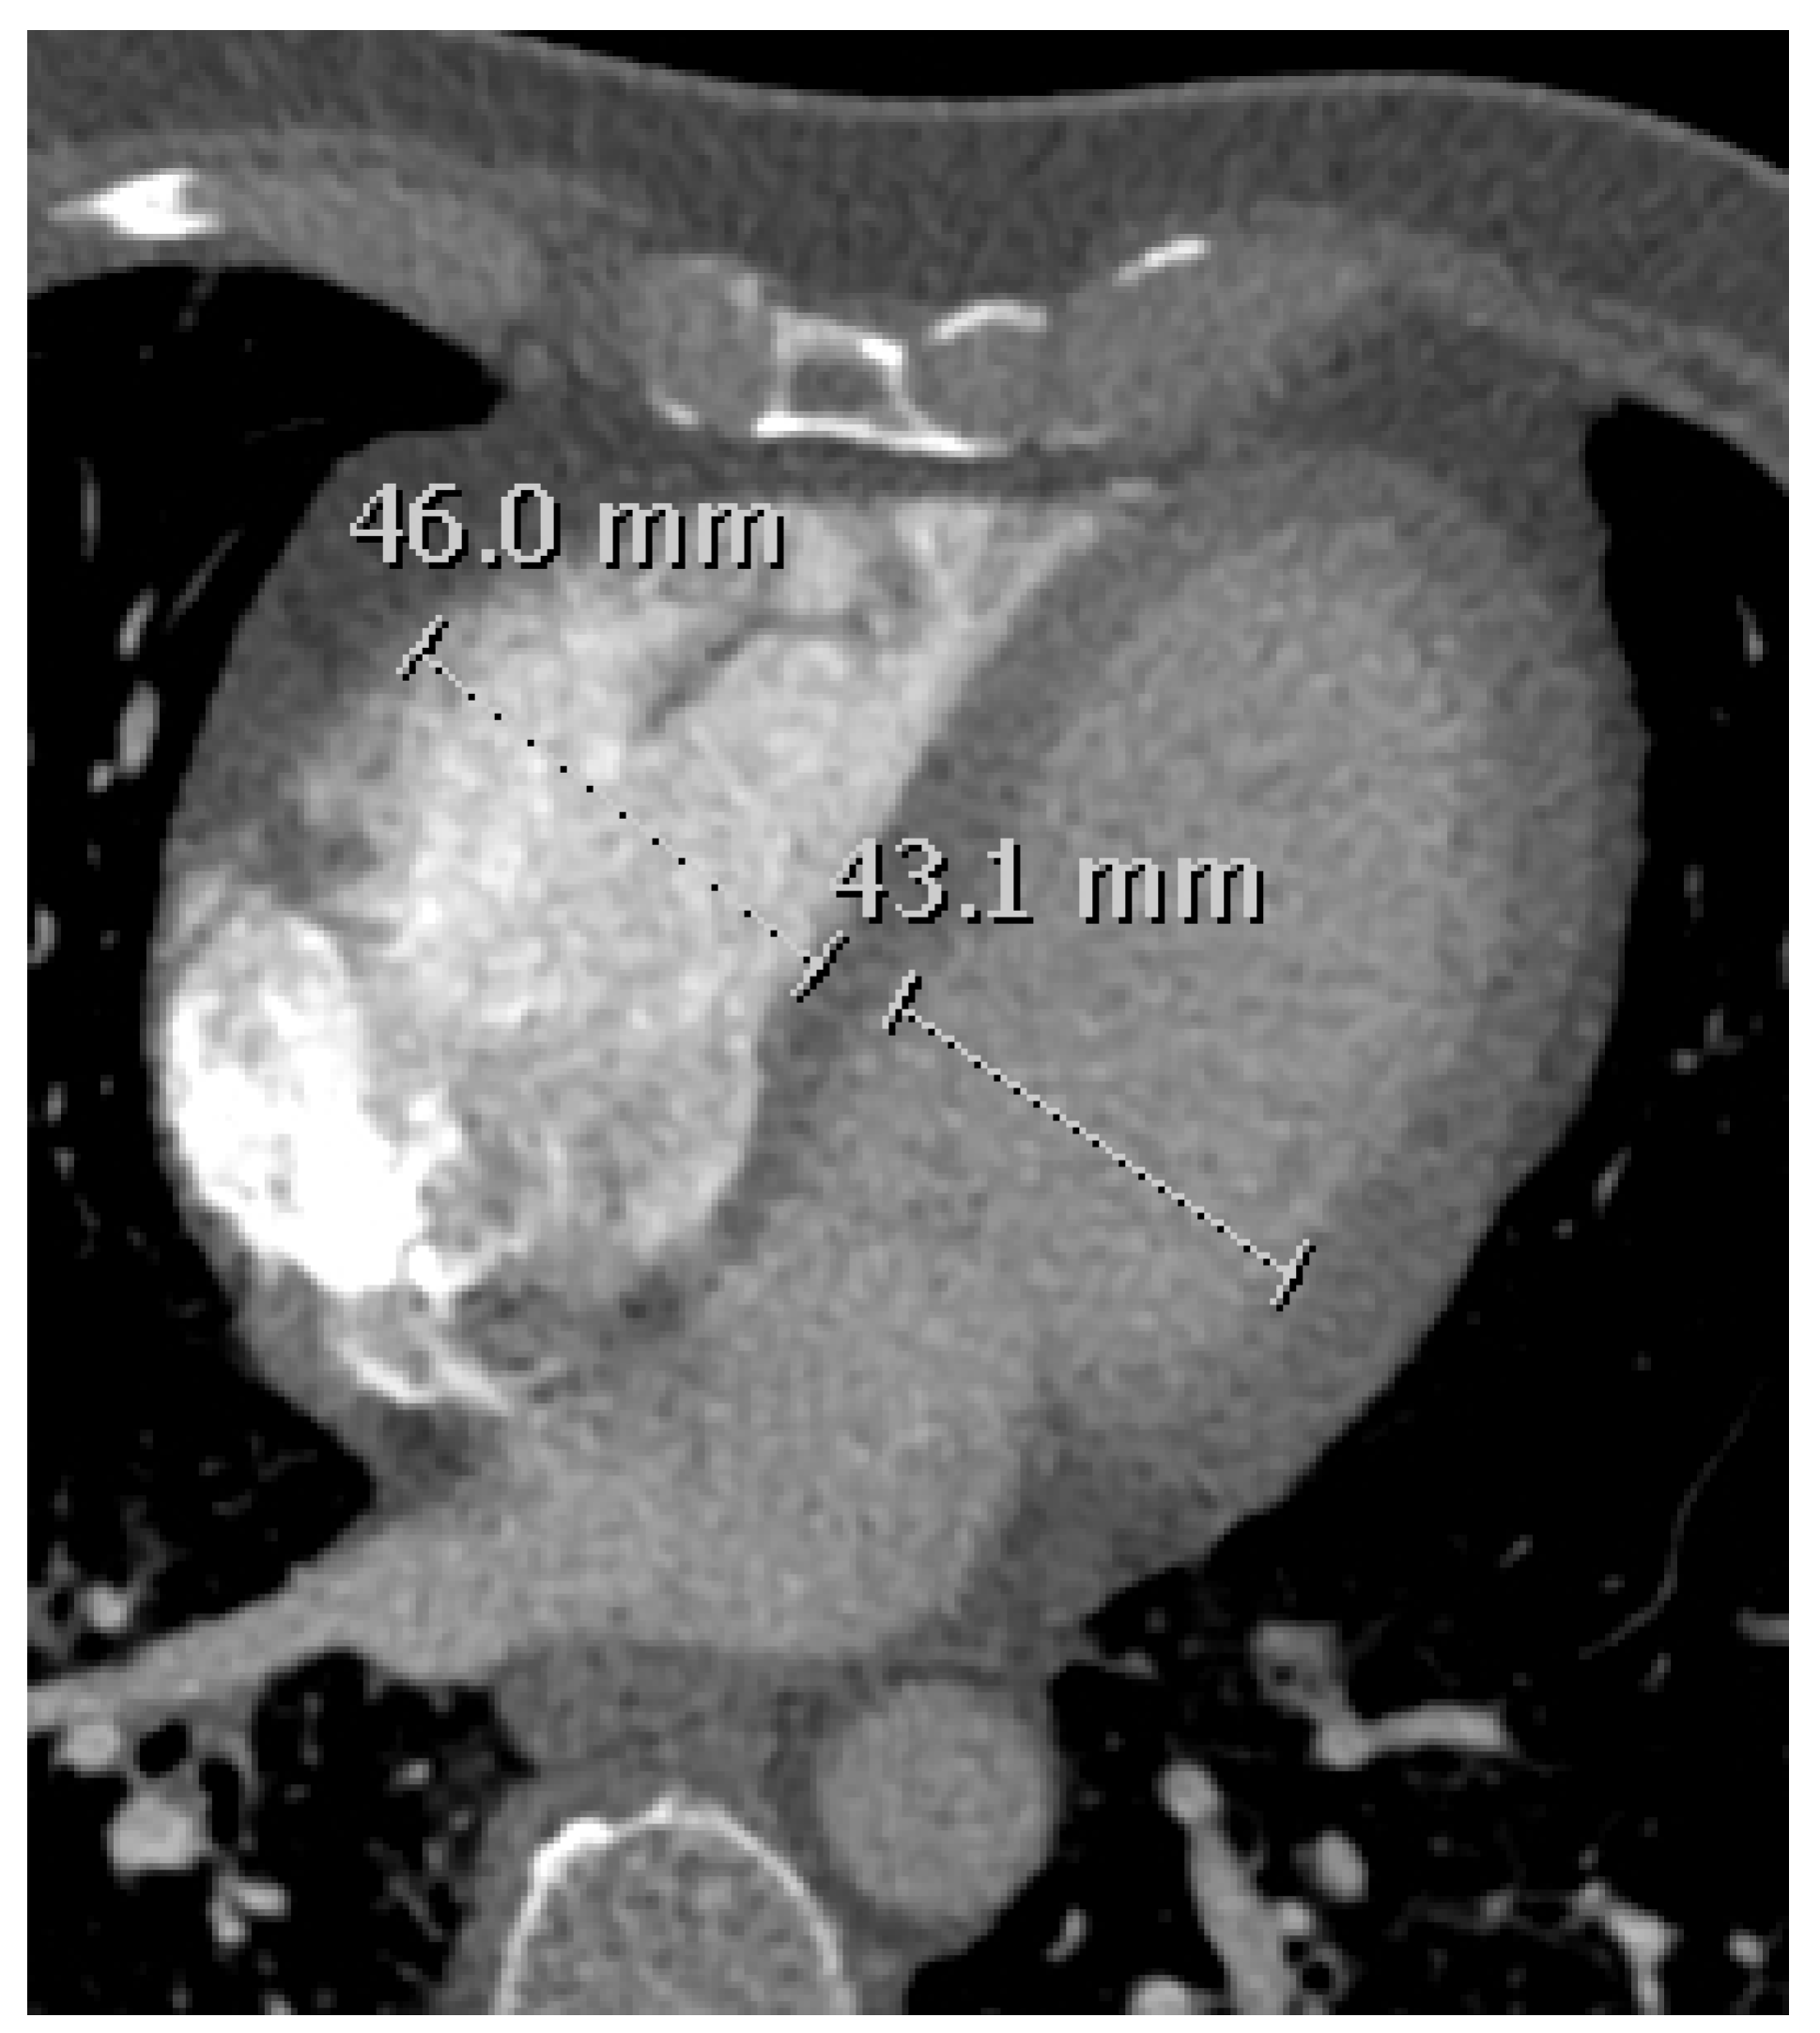

2.5. RVD Assessment